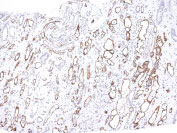

Formalin-fixed, paraffin-embedded human Kidney Transplant stained with Complement 4d Monoclonal Antibody (C4D204).